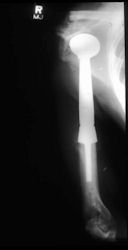

Examples of radical limb sparing surgeries for osteosarcomas in various anatomic locations (distal femur, proximal tibia, proximal humerus, scapula)

In each case, the tumor and bone from which it arose were resected. This required meticulous dissection, mobilization and preservation of adjacent pertinent neurovascular structures. In each case presented here, the defect was reconstructed with a special modular segmental tumor prosthesis. This also replaces the adjacent joint in many instances.

| Limb-sparing surgery for osteosarcoma of distal femur – Plain Xrays |

Postoperative X-Rays